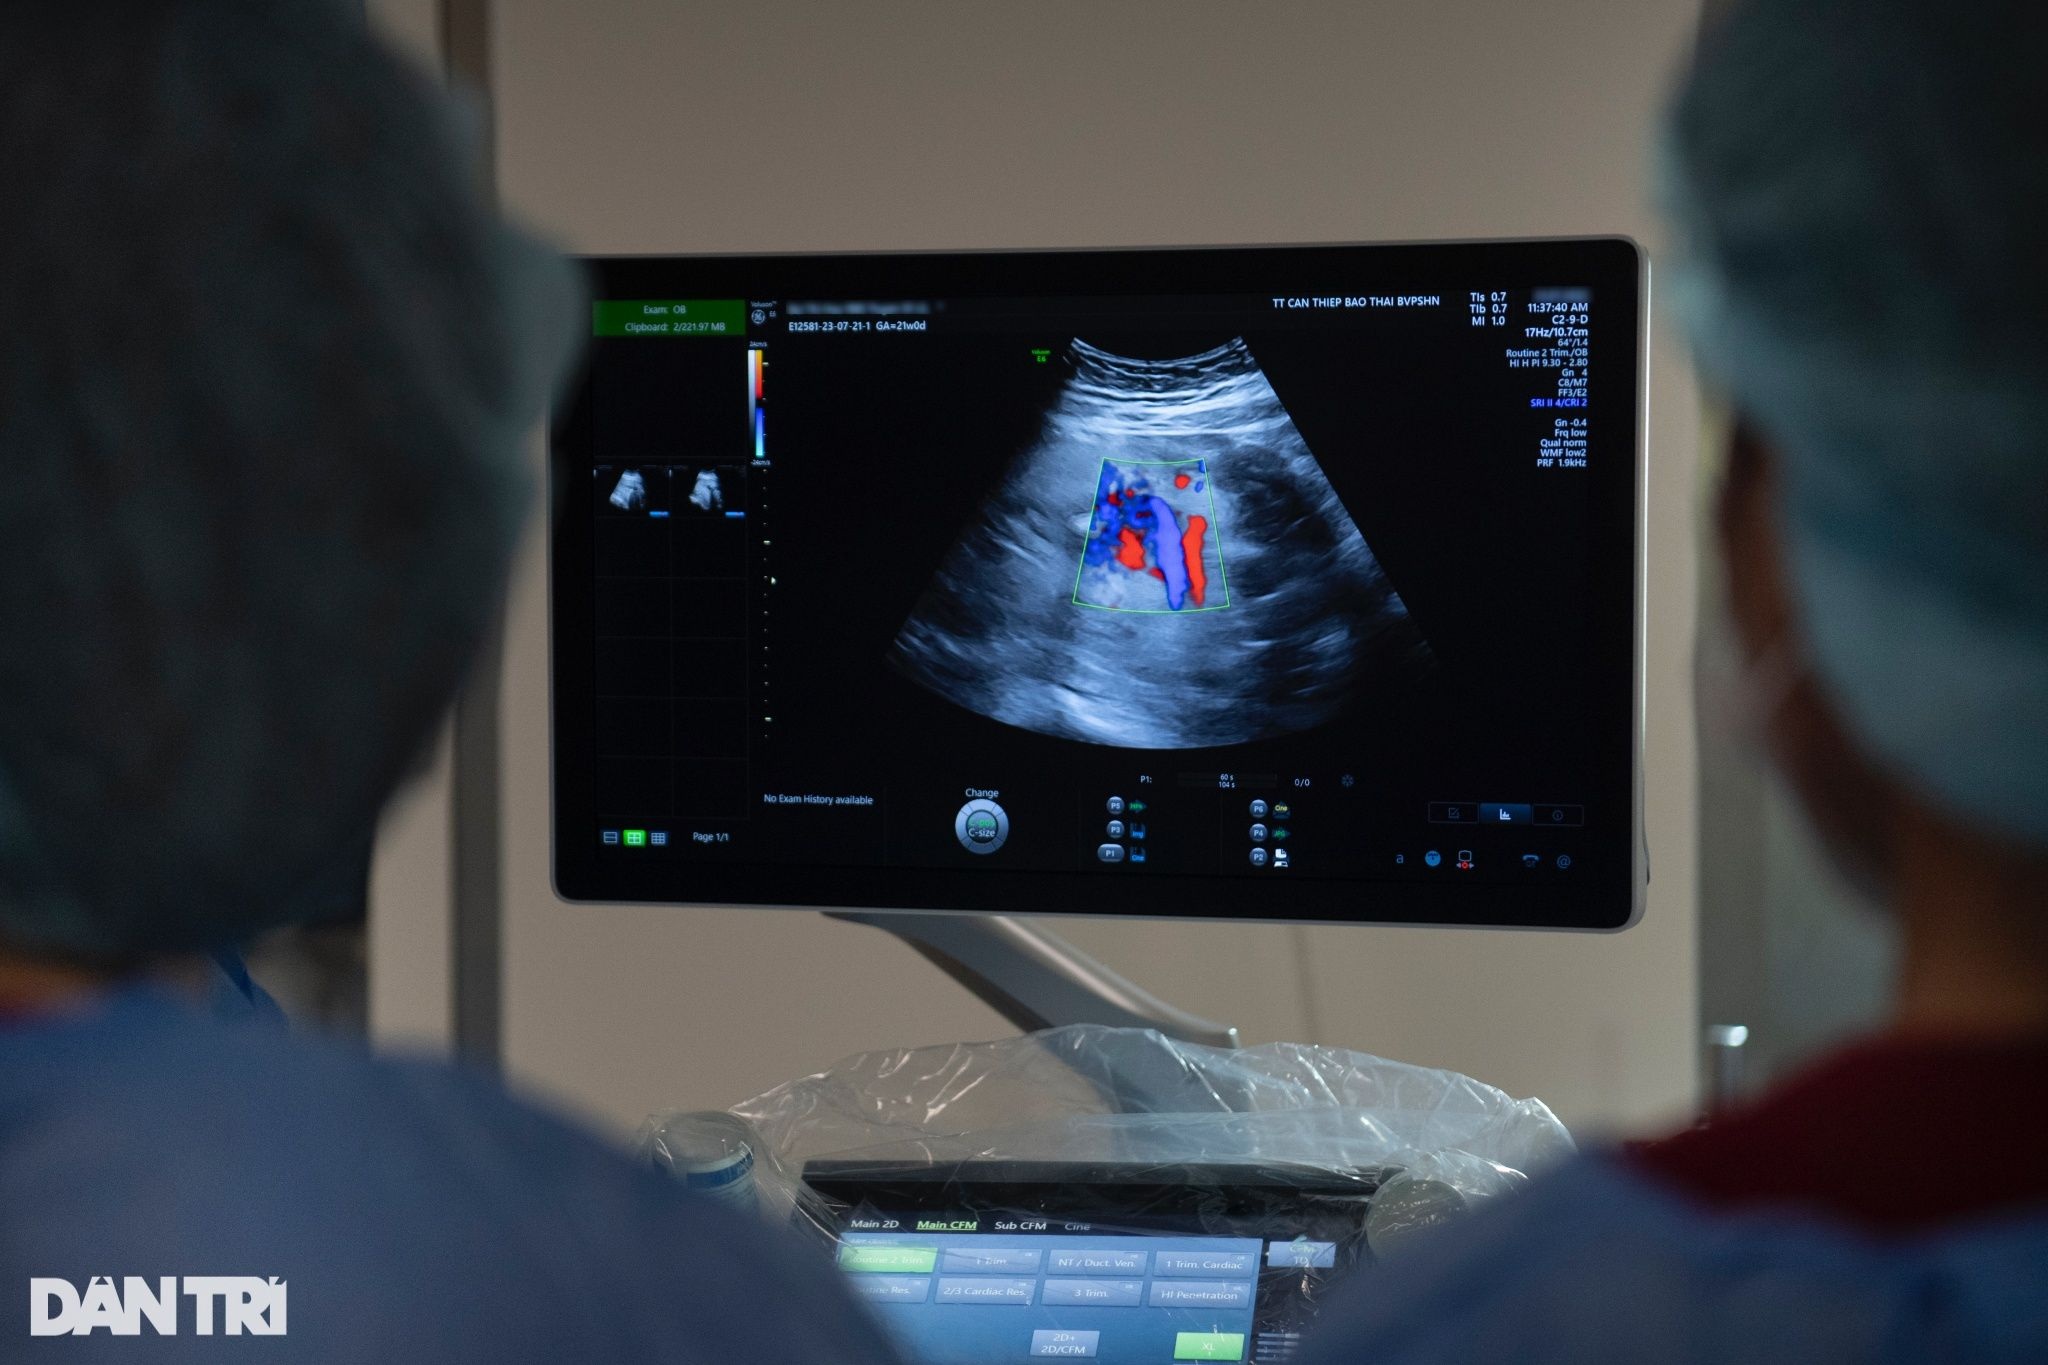

Dừng lại tại vị trí vùng cổ của thai nhi, BS Sim xác định đây sẽ là vị trí tiếp cận đầu tiên. Sau khi kích hoạt cửa sổ dopler, 2 mảng màu xanh đỏ hiện lên trên màn hình máy siêu âm.

"Với sản phụ cạn ối, dây rốn cũng sẽ ép chặt vào những khe hõm còn lại như vùng cổ hoặc chân, tay. Thông qua sự hỗ trợ của cửa số dopler cùng với kinh nghiệm, chúng tôi sẽ nhận diện được vị trí của dây rốn để tránh đưa kim vào", BS Sim lý giải.